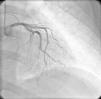

Ao exame objetivo apresentava-se hemodinamicamente estável e sem alterações relevantes. O eletrocardiograma (ECG) de 12 derivações mostrava taquicardia sinusal, com infra-ST em V4, ondas T negativas em V4-V5 e aplanadas em V6 e derivações frontais (Figura 1). Os testes laboratoriais revelaram hemoglobina 11,3g/dL, velocidade de sedimentação 84mm, proteína C reativa 6,14mg/dL, troponina I 1,89 ng/dL (com discreta subida na segunda determinação para 2,02 ng/mL) e CK-mb 8,4 ng/mL, pelo que foi internada na Unidade Coronária com o diagnóstico de EAM sem elevação do ST. O ecocardiograma transtorácico revelou compromisso moderado a grave da função sistólica do ventrículo esquerdo, com acinésia apical e hipocinésia dos segmentos mesoapicais das paredes anterior, lateral e septo interventricular. Além das alterações da contratilidade segmentar, observou-se uma volumosa massa auricular esquerda fixada ao septo interauricular, de estrutura coraliforme e aspeto friável, com cerca de 46mm de maior eixo, cuja porção mais apical prolapsava para o ventrículo esquerdo em diástole sobre o folheto anterior da válvula mitral, não condicionando obstrução fixa ao fluxo de câmara de entrada do VE (Figura 2). Dada a elevada probabilidade de se tratar de um mixoma, realizou de imediato ecocardiograma transesofágico (Figura 3), que confirmou os achados descritos em transtorácico, pelo que, mediante a possibilidade de embolização eminente, foi contactado o Serviço de Cirurgia Cardiotorácica do nosso hospital de referenciação, que aceitou receber a doente após realização de angiografia coronária, a qual mostrou artérias coronárias sem lesões angiograficamente significativas (Figura 4).

Nos casos de mixomas cardíacos que se apresentam com enfarte agudo do miocárdio, é pertinente a realização de angiografia coronária para investigação de doença coronária, especialmente em doentes com idade superior a 40 anos ou com fatores de risco cardiovascular. Tem sido documentada a embolização nas artérias coronárias descendente anterior e circunflexa, embora a embolização para a coronária direita seja mais prevalente, possivelmente devido à posição anatómica relativamente favorável do ostia da coronária direita em relação ao fluxo aórtico. Num número não desprezível de casos não foram encontradas lesões coronárias por angiografia, o que pode ser justificado pela elevada taxa de recanalização das embolias coronárias a partir de mixomas6.